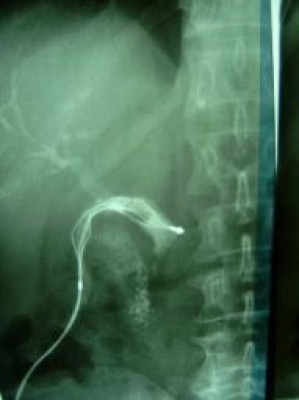

Extracción percutánea de cálculo de coledoco

Envíado por Dr. Carlos Miguel Zavaleta Consuegra